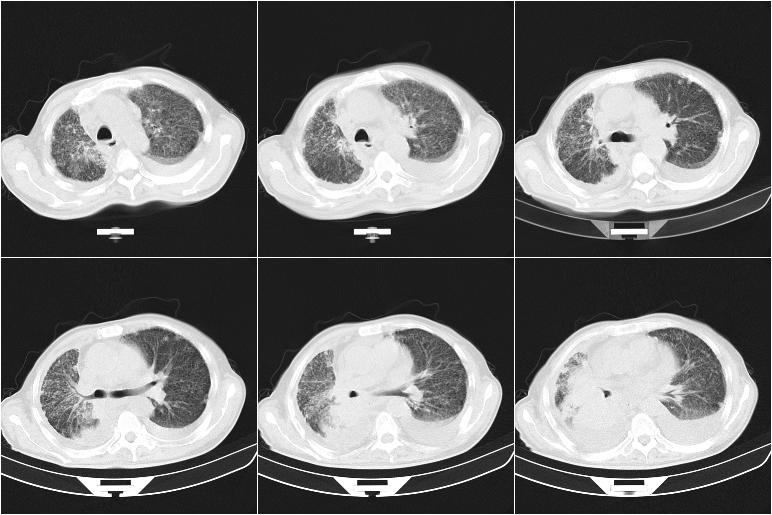

以下是引用边生丽在2009-8-17 11:43:00的发言:[br][br] [br] 右肺中心型癌伴右肺下叶不张、双肺转移并癌性淋巴管炎、心包和双侧胸腔积淮(转移?)、脑转移、肝转移、多骨(颅骨、椎骨)转移。 [br] [br]

以下是引用随光逐影在2009-8-17 14:09:00的发言:[br]支持 右肺中央型癌伴右肺下叶肺不张,纵隔淋巴结转移,双肺转移并癌性淋巴管炎,心包和双侧胸腔积液,脑转移、肝转移、多发性骨(颅骨、脊椎)转移。